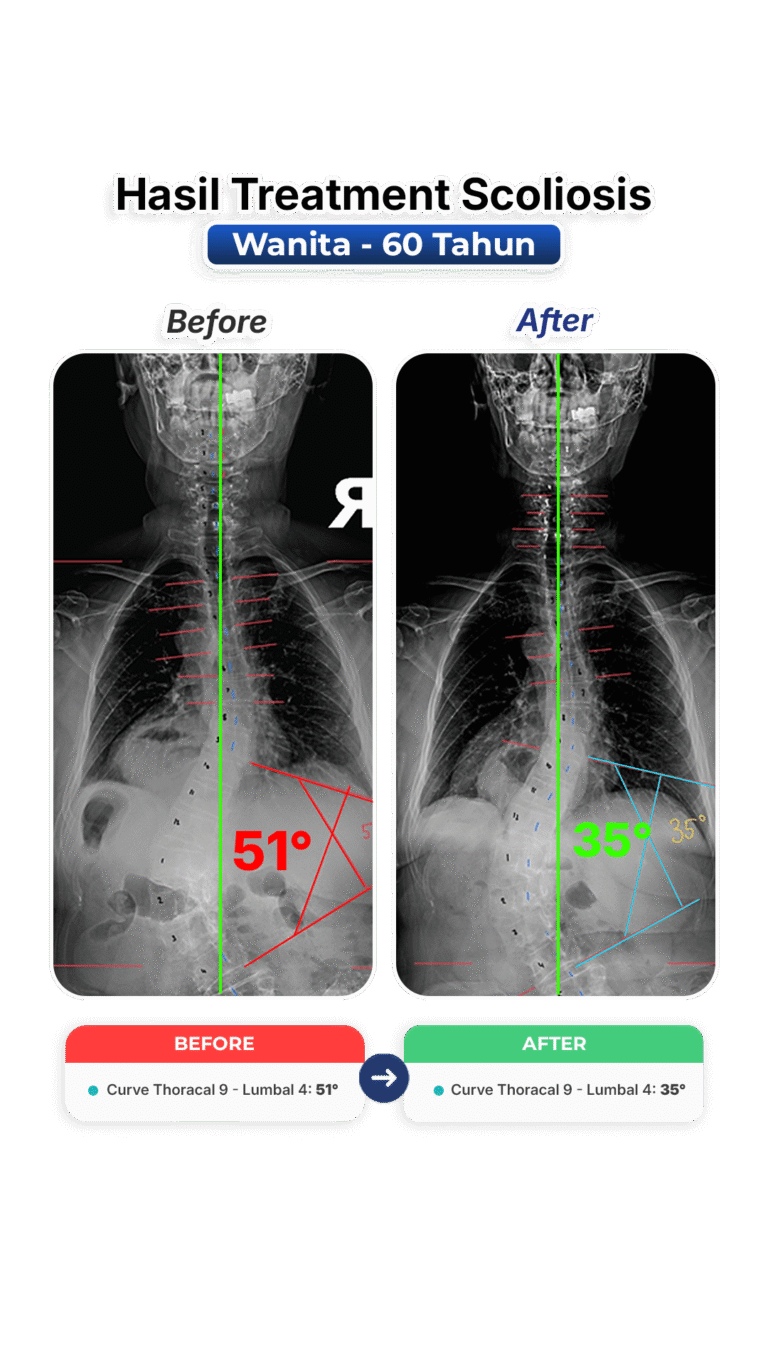

Perubahan nyata setelah mengikuti program terapi skoliosis di VLife Medical Galaxy Mall 3.

Perawatan scoliosis dilakukan melalui evaluasi tulang belakang menyeluruh, program terapi bertahap, fokus keseimbangan postur, mengurangi nyeri, memperlambat progres kelengkungan, serta meningkatkan fungsi gerak harian pasien secara aman dan terkontrol medis.

Penanganan skoliosis berbasis evaluasi postur menyeluruh, terapi manual khusus, latihan koreksi, serta pemantauan progres di setiap sesi. Dibuat untuk remaja dan dewasa yang ingin mengendalikan kelengkungan skoliosis dan mengurangi nyeri.